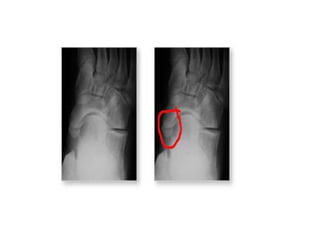

X-rays

• AP, lateral, internal oblique and external

oblique view.

–

The accessory ossicle may be best

visualized on the internal oblique view(reverse

oblique view).